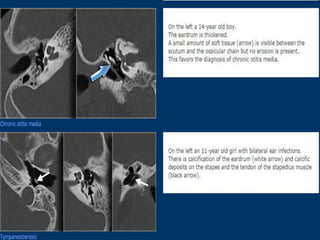

5. Tympanosclerosis.

It is seen as white chalky deposit on the promontory, ossicles,

joints, tendons and oval and round windows and interfere with

the mobility of these structures and cause conductive deafness.